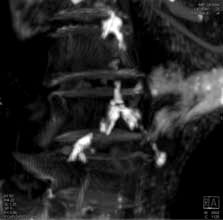

While atherosclerosis has been observed before in ancient Egyptians, this study found it to be more prevalent than previously thought. The interdisciplinary team performed whole body computerized tomography (CT) scans on 52 ancient Egyptian mummies to determine if atherosclerosis was present. Of the 44 with identifiable arteries or hearts, nearly half (45 percent) had calcifications either in the wall of an artery or along the course of an artery that are diagnostic of or highly suggestive of atherosclerosis. “Commonly, we think of coronary artery or heart disease as a consequence of modern lifestyles, mainly because it has increased in developing countries as they become more westernized,” said Gregory S. Thomas, M.D., MPH, clinical professor and director of nuclear cardiology education, University of California, Irvine and the study’s co-principal investigator.

“These data point to a missing link in our understanding of heart disease, and we may not be so different from our ancient ancestors.” Most of the atherosclerosis was found in the large arteries of the body, including the aorta in the abdomen. However, key smaller arteries were also involved. About 7 percent of the mummies had obstructions in the heart arteries, and 14 percent had blockages in the arteries to the brain, the carotid arteries, which is a leading cause of stroke in the present day. Researchers also found that, similar to now, advancing age was highly predictive of the presence and severity of atherosclerosis.

Thomas explains that the calcific atherosclerosis seen with CT scanning looks just like the atherosclerosis of today and appears in the same locations. While researchers could not determine the exact cause of death in these mummies, symptoms consistent with cardiac chest pain had been described in ancient Egyptian scrolls. In order to understand the lifestyles of ancient Egypt’s elite, the team of researchers worked with Egyptologists to review risk factors that might affect the health of the heart and arteries.